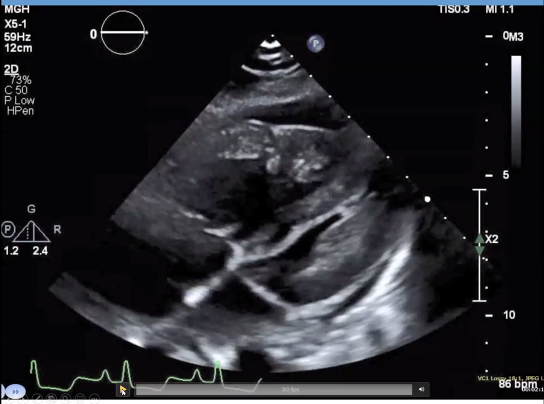

Undergoes a TTE at OSH, here's a still:

Both ventricles but RV in particular is hypertrophied and dilated, RVSP 91, + pericardial effusion.

Back to the case: PA pressures as below, and TEE performed with concern for RV outflow tract obstruction

It's the fateful "suicide RV"

But in this patient, given her R heart disease, ended up with post transplant RVOT obstruction from relative reduction in PA pressures!